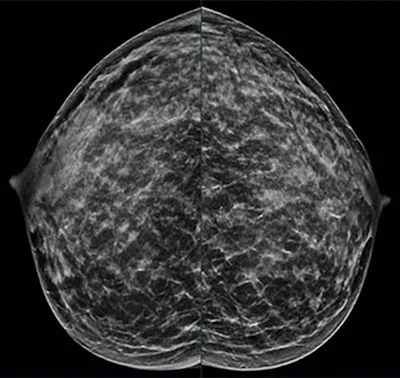

Пациентка 40 лет обратилась на плановый скрининг, в семейном анамнезе имеется бабушка по отцовской линии, 55 лет. При маммографии в правой и левой краниокаудальной проекции отмечена чрезвычайно плотная ткань молочной железы.РСНА